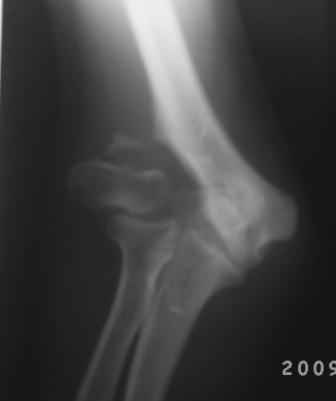

Вы очень конкретно и правильно поставили вопросы и очень аргументированно анализировали, смысл мне понравился, дело в том что у меня был случай 4-года назад. Б-ная 18 лет, травму получила в детстве, клиника точно такая, только движения в плече-лучевом суставе была сохранена, произведена клиновидная надмышелковая остеотомия, фиксация спицами и тогда была наложена гипсовая повязка на 1,5месяца, разработка движений начался очень хорошо, и она уехала в другой город, где оказывается удалили спицы и она доволно результатом.( ложный сустав латераль. мышелка так и осталось и ей не мешает!)

Для интереса представляю снимки.